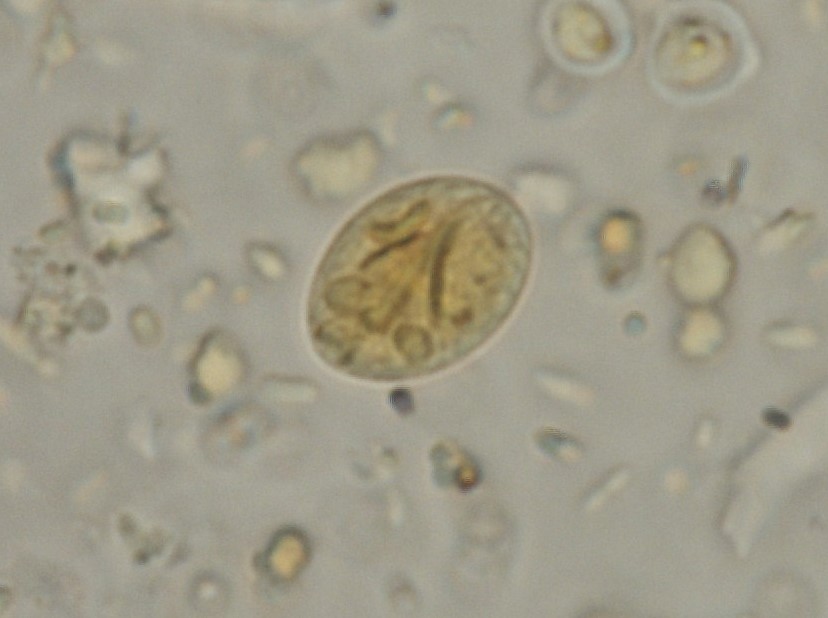

Giardia duodenalis est un protozoaire flagellé ubiquiste et très commun infectant les mammifères dont l’Homme. Ce parasite est considéré comme un complexe d’espèces comprenant huit assemblages identifiés de A à H, certains assemblages étant plus spécifiques d’hôtes. Le cycle biologique est très simple et comprend un stade trophozoïte chez l’hôte et un stade kyste infectieux dans l’environnement. La période prépatente (période comprise entre l’ingestion de kystes par l’hôte et le début d’excrétion des kystes dans les fèces) est de l’ordre de 6 à 10 j. Giardia est retrouvé plus fréquemment chez les jeunes ruminants (ou pré-ruminants) avec un début d’excrétion autour de quelques jours d’âge, un pic de prévalence entre 2 et 6 mois et une fréquence d’excrétion plus faible et irrégulière au-delà de 6 mois. Les facteurs de risque d’infection sont le jeune âge, le contact avec la mère, des défauts dans le nettoyage et la désinfection des locaux, un déficit de transfert colostral et la saison. Cliniquement, la giardiose se manifeste par une diarrhée chronique, intermittente, accompagnée d’une excrétion de kystes irrégulière. Il faut cependant souligner que la majorité des études mettent en évidence l’importance des infections asymptomatiques chez les ruminants et ce, quel que soit le niveau d’excrétion de kystes. Le diagnostic de giardiose chez les veaux est complexe en raison d’une non simultanéité entre signes cliniques et excrétion de kystes (contrairement à Cryptosporidium par exemple). Parmi les nombreuses techniques diagnostiques existantes, on privilégiera la technique la plus sensible. En raison d’une recontamination fréquente des animaux après traitement, le contrôle de la giardiose s’appuie principalement sur des mesures hygiéniques (propreté des litières et désinfection).